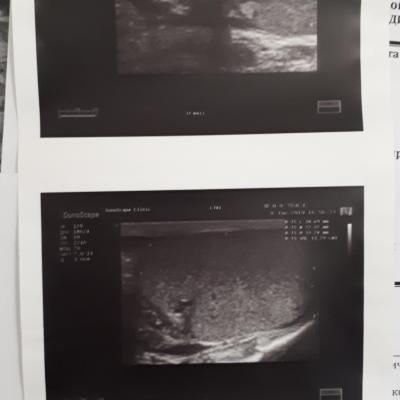

здравствуйте, периодически беспокоят боли в правом яичке, обращался к трём урологам, сдавал на разные инфекции , ничего нет, по УЗИ поставили диагноз хр. эпидидимит, после назначенного не заметил сильного улучшения, боли возвращаются, последний врач к которому обратился сказал будут боли , свечи вольтарен и все. Есть ли лечение при обострении этой болезни? Как мне самому кажется первые боли появились после не сильного удара по правому яичку.